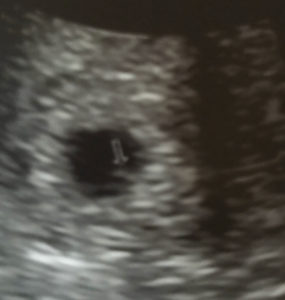

Clarksville TN Essure Reversal Pregnancy Off To Great Start!

Early Tennessee Essure Reversal Baby

I had my ultrasound done today at 5wks and 5days.

The baby is in my uterus!

Patient age: 33

Tubal ligation type: Essure

Patient hometown: Clarksville, Tennessee